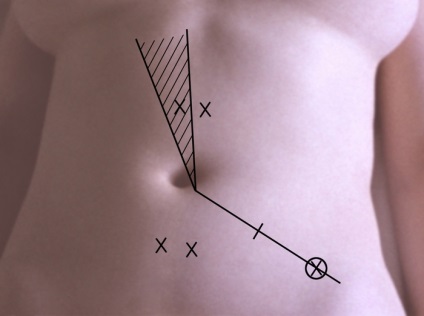

Az első lépés a bevezetése pneumoperitoneum L. a. A hasat kilyukadt egy speciális tű (a tű típusától Leriche) a bal alsó pont nyomkövetés (ábra. 1). A hasüreget adjuk 3000-4000 cm3 levegőt. dinitrogén-oxid vagy szén-monoxid. Attól függően, hogy a célkitűzések a tanulmány beadásra laparoszkópon egyik kiválasztott pontok szerinti rendszer felkutatása gyakran fent és bal oldalán a köldök. Szike, hogy egy bőr bemetszést 1 cm. Boncolással a bőr alatti szövet, és a fascia a rectus abdominis. Ezután, a hüvely trokár szúrja a hasfal, a trokár eltávolítják, és ezen keresztül a hüvely kerülnek bevezetésre laparoszkópot. Ellenőrzés a has szakaszosan végezzük jobbról balra, megtekintésekor a jobb oldali csatorna, a máj, obstruktív és mellékvese térben szubdiafragmatikus helyet. bal oldalsó csatornát medencét. Meg lehet változtatni a helyzetét a beteg részletesebb ellenőrzést. A színe, jellege a felület, az alak a test átfedések, hiszen folyadékgyülem lehet beállítani lézió jellege: májzsugor (2A ábra.) Metasztatikus (2b ábra.), Heveny gyulladás (2. ábra, d.) nekrotikus folyamat (ábra. 2, stb), stb A diagnózis megerősítésére biopszia (általában egy defekt). Széles körben használják különböző orvosi eljárásokban L. hasi vízelvezető (3A.), Mikroholetsistostomiya (ábra. 3b), és mások. Lezárását követően laparoskipii laparoskona és extrahálás a hasüregből a gáz eltávolítása után a bőrön sebet lezárjuk 1- 2 öltés.

Ábra. 1. Klasszikus nyomkövetés pont alkalmazása pneumoperitoneum és bevezetése laparoszkópot: a beadás helyén laparoszkópon jelölt kereszt, szúrás helyére pneumoperitoneum jelzi egy kört, árnyékos vetülete kör szalag a májban.